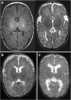

Abnormal configuration of cerebral ventricles

Tuberous sclerosis complex (TSC) is a rare multisystem autosomal dominant genetic disease that causes non-cancerous tumours to grow in the brain and on other vital organs such as the kidneys, heart, liver, eyes, lungs and skin. A combination of symptoms may include seizures, intellectual disability, developmental delay, behavioral problems, skin abnormalities, lung disease, and kidney disease. [Source: Wikipedia ]